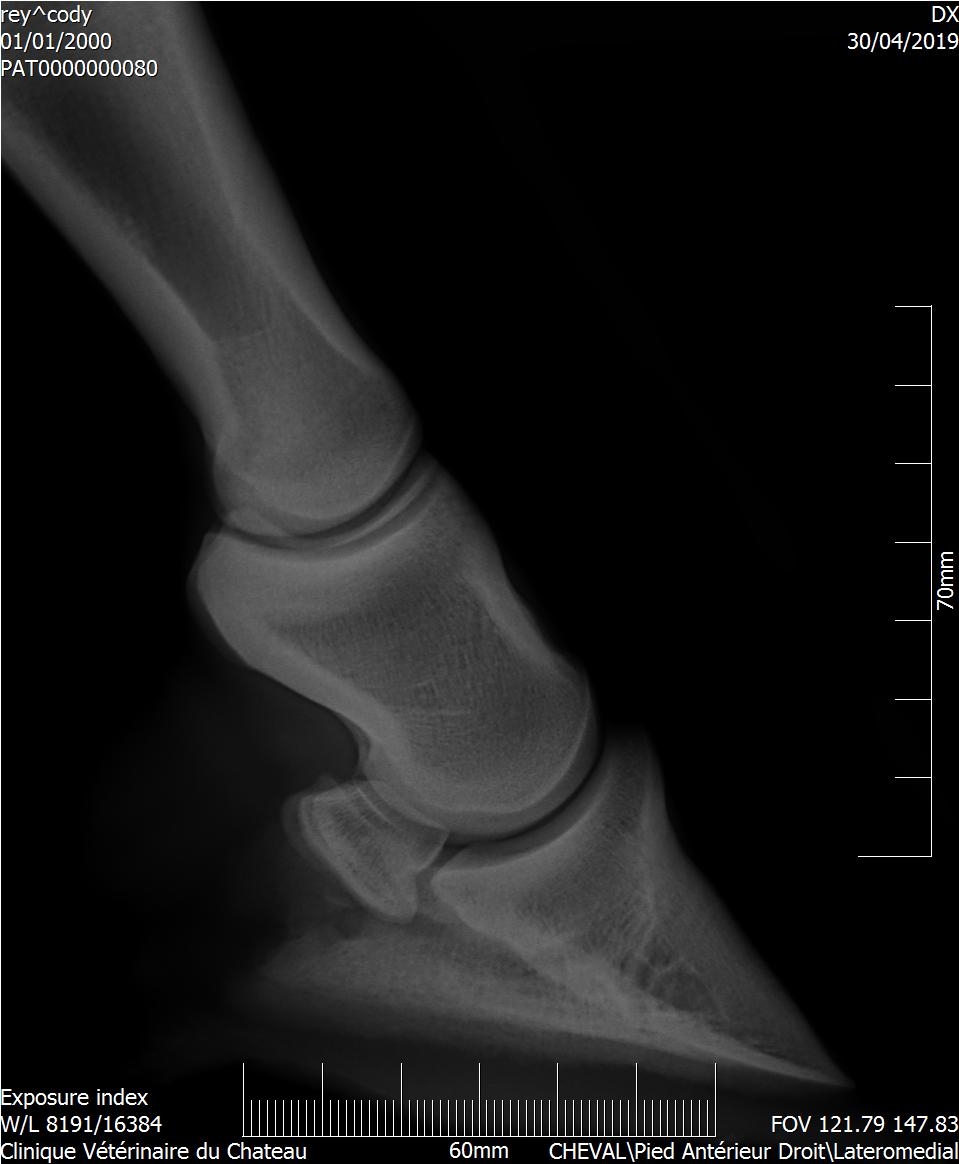

| Dire merci | Pour donner un ordre d'idée : radio de Cody.![]() |

| Dire merci | Disons que ça dépend ce qu'il voulait voir, s'il voulait les articulations c'est bon, s'il voulait une photo du pied c'est coupé c'est clair ! Mais je pense qu'il cherchait une photo des articulation, sur une photo de pied l'articulation du boulet est souvent coupée (cf radio de cody) Elle est bizarre d'ailleurs ta radio goss, on voit pas du tout la boîte cornée |

| Dire merci | La radio a été prise pour voir le naviculaire. J'en ai d'autres ![]() ![]() ![]() |